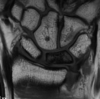

Cisto ósseo aneurismático

Acomete paciente jovem (fise aberta);

Localização excêntrica, aspecto em favo de mel no RX;

Pode ter reforço periosteal;

RM:lesão multicística; Septos + nível liquido-liquido (lesões dx diferencial: COS fraturado, COA, TCG ou osteossarcoma telangiectásico).

Primário ou Secundário à outros tumores: TCG, DF, Condroblastoma.